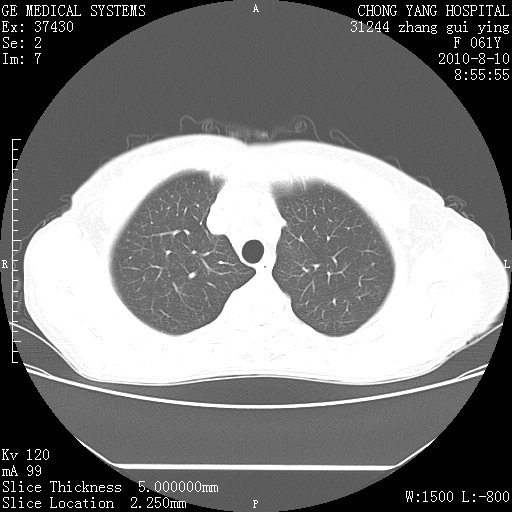

标题: CT28314:F61Y胸部增强,发热咳嗽一周入院,后面的为一周前平

1、支持考虑右侧中央型肺癌伴右肺中叶节段性不张及下叶支气管黏液痰栓    2、左肺上叶舌段感染。

支持右下肺中央型肺癌并左上肺感染.

确切的说:1:右肺下叶中心型肺癌侵及中叶支气管并中叶不张,纵膈淋巴结转移。2:左肺舌叶炎症。3:右侧胸腔少量积液

右肺下叶内基底段近膈不规则肿块,考虑右肺下叶周围型肺癌可能性大。